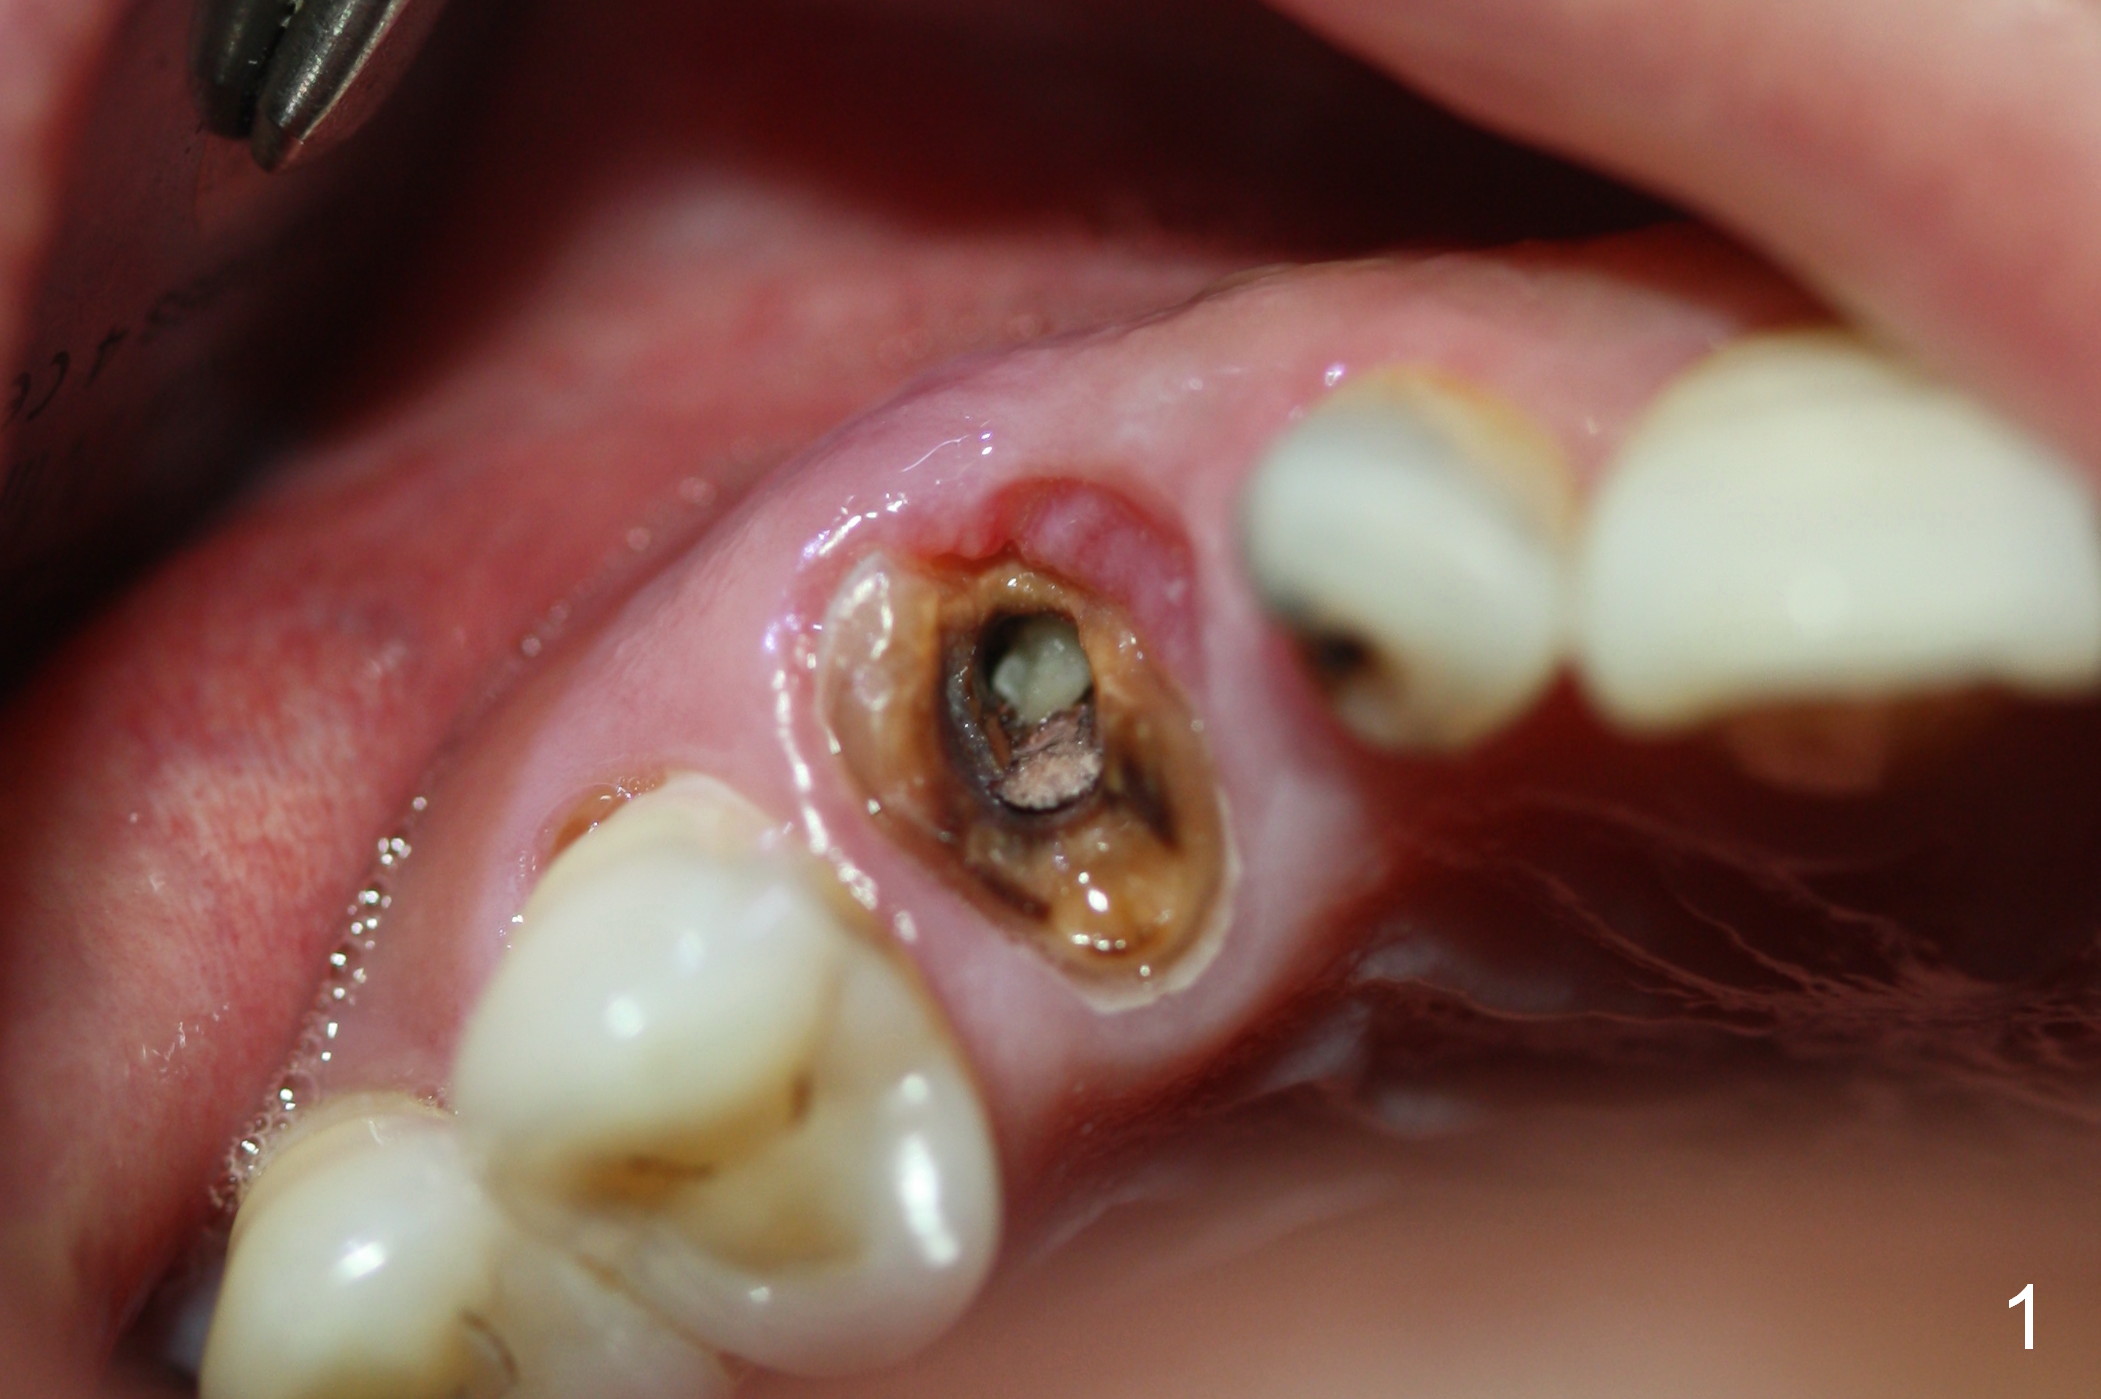

While the periodontal ligament is being severed with Proximators (periotomes), the tooth #6 is found closer to the tooth #5 (Fig.1,2). When the tooth is extracted, an osteotomy is initiated slightly mesially in the palatal wall of the socket (Fig.3 O).